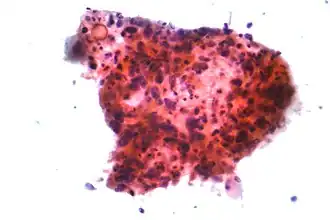

Longkanker wordt geclassificeerd naar histologisch type, dit is het oorspronkelijke celtype waaruit de kanker is ontstaan.[14] Deze classificatie is van belang voor bepaling van de behandeling en het voorspellen van het verloop van de ziekte. Verreweg de meeste vormen van longkanker zijn carcinomen, kwaadaardige tumoren die ontstaan vanuit epitheelcellen. Longcarcinomen worden ingedeeld naar de grootte en het uiterlijk van de kwaadaardige cellen zoals een histopatholoog die onder een microscoop ziet. Er wordt een globale tweedeling in niet-kleincellige en kleincellige longcarcinomen gebruikt.[36]

Bij het kleincellige longkanker (SCLC) bevatten de cellen dichte neurosecretoire korrels (vesikels die neuro-endocriene hormonen bevatten), waardoor deze tumor gepaard gaat met een endocrien/paraneoplastisch syndroom (een reeks verschijnselen die wordt veroorzaakt doordat de kanker zelf hormonen afscheidt).[39] De meeste gevallen doen zich voor in de grote luchtwegen (primaire en secundaire bronchiën).[16] Deze kwaadaardige tumoren groeien snel en zorgen in een vroeg stadium van de ziekte voor uitzaaiingen. Zestig tot zeventig procent is al uitgezaaid wanneer de kanker merkbaar wordt. Dit type longkanker hangt sterk samen met roken.[2]

Primaire longkanker zaait vaak uit naar de hersenen, botten, de lever en de bijnieren.[9] Immunokleuring van een biopsie helpt vaak de oorspronkelijke bron te vinden.[42]